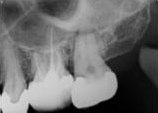

antes depois